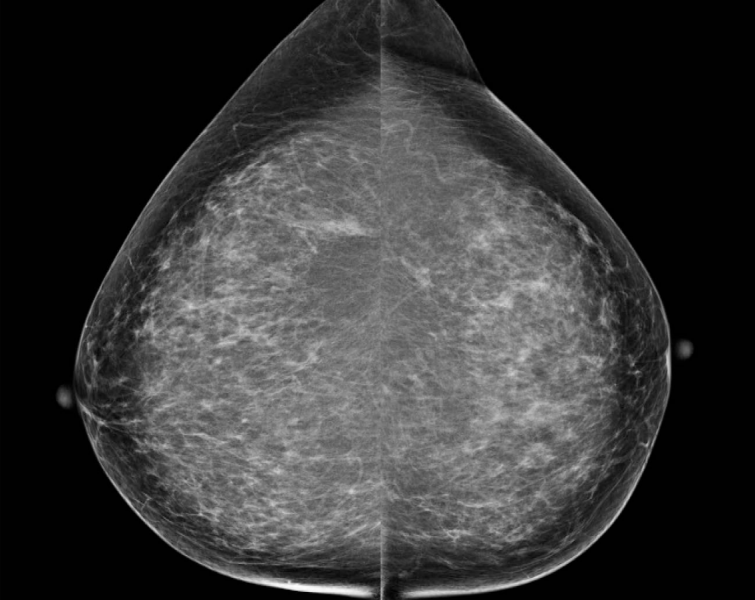

Patient 1: Bilateral MLO views from screening mammography in a 53-year-old woman.